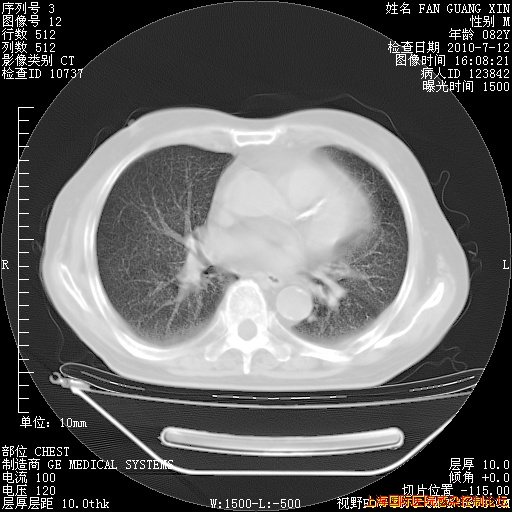

补发6月12日肺部CT肺窗

6月12日肺窗

整整相隔30天的肺部CT好像有所好转啊。甲强龙减量第3天,需要观察体温。